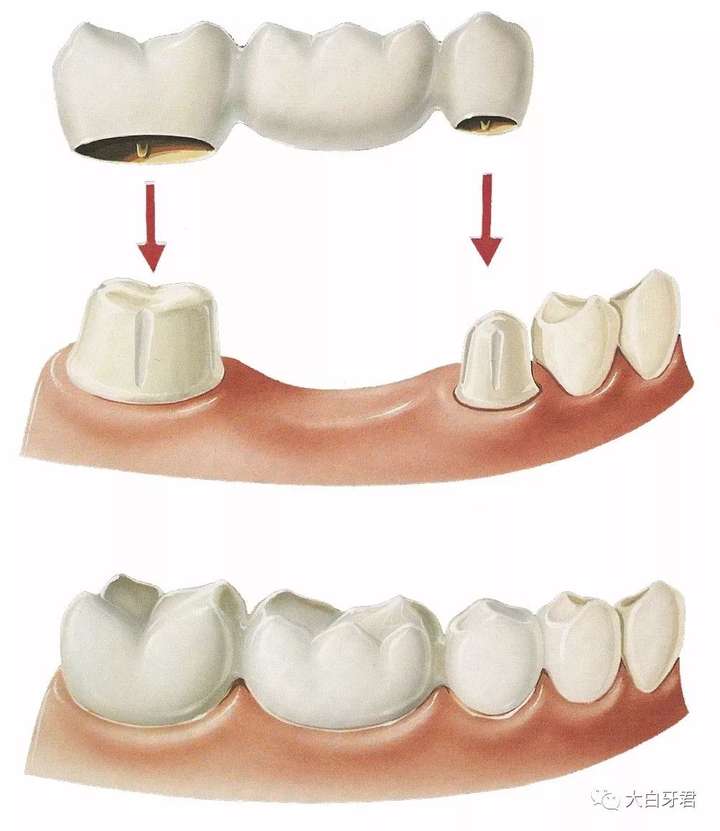

这就是全文开始的时候一个病人对于自己缺牙之后,医生提供的方案之一。这个「三」是怎么回事?

其实,缺了一个牙,如果觉得经济有压力,做不起一两万的种植牙,但是又觉得活动假牙不舒服,也可以选择「固定桥」的方案来做修复。

如果我们把空隙两边的牙齿磨小一圈,将三个牙冠连成一体制作,最后通过两端磨小的天然牙作为「桥墩」,缺牙空隙上方的牙冠就是「桥体」,这样才能让这个空缺位置的假牙牢固地和两侧的天然牙相连。

缺一个牙,利用两侧天然牙「搭桥」

缺一个牙,利用两侧天然牙「搭桥」

这就是为什么缺一个牙要「补」三个牙。

自然,细心的大白牙君的朋友们肯定也已经发现——我为了修补缺失的一个牙齿,却多「损伤」了两遍的健康牙齿,是不是太可惜了?

摸着良心讲,大白也觉得可惜,但这种修复方案并不是错的,甚至对于某些人来说是最佳的选择。这种方法的优势就在于:时间短、价格相对低、舒适性尚可。